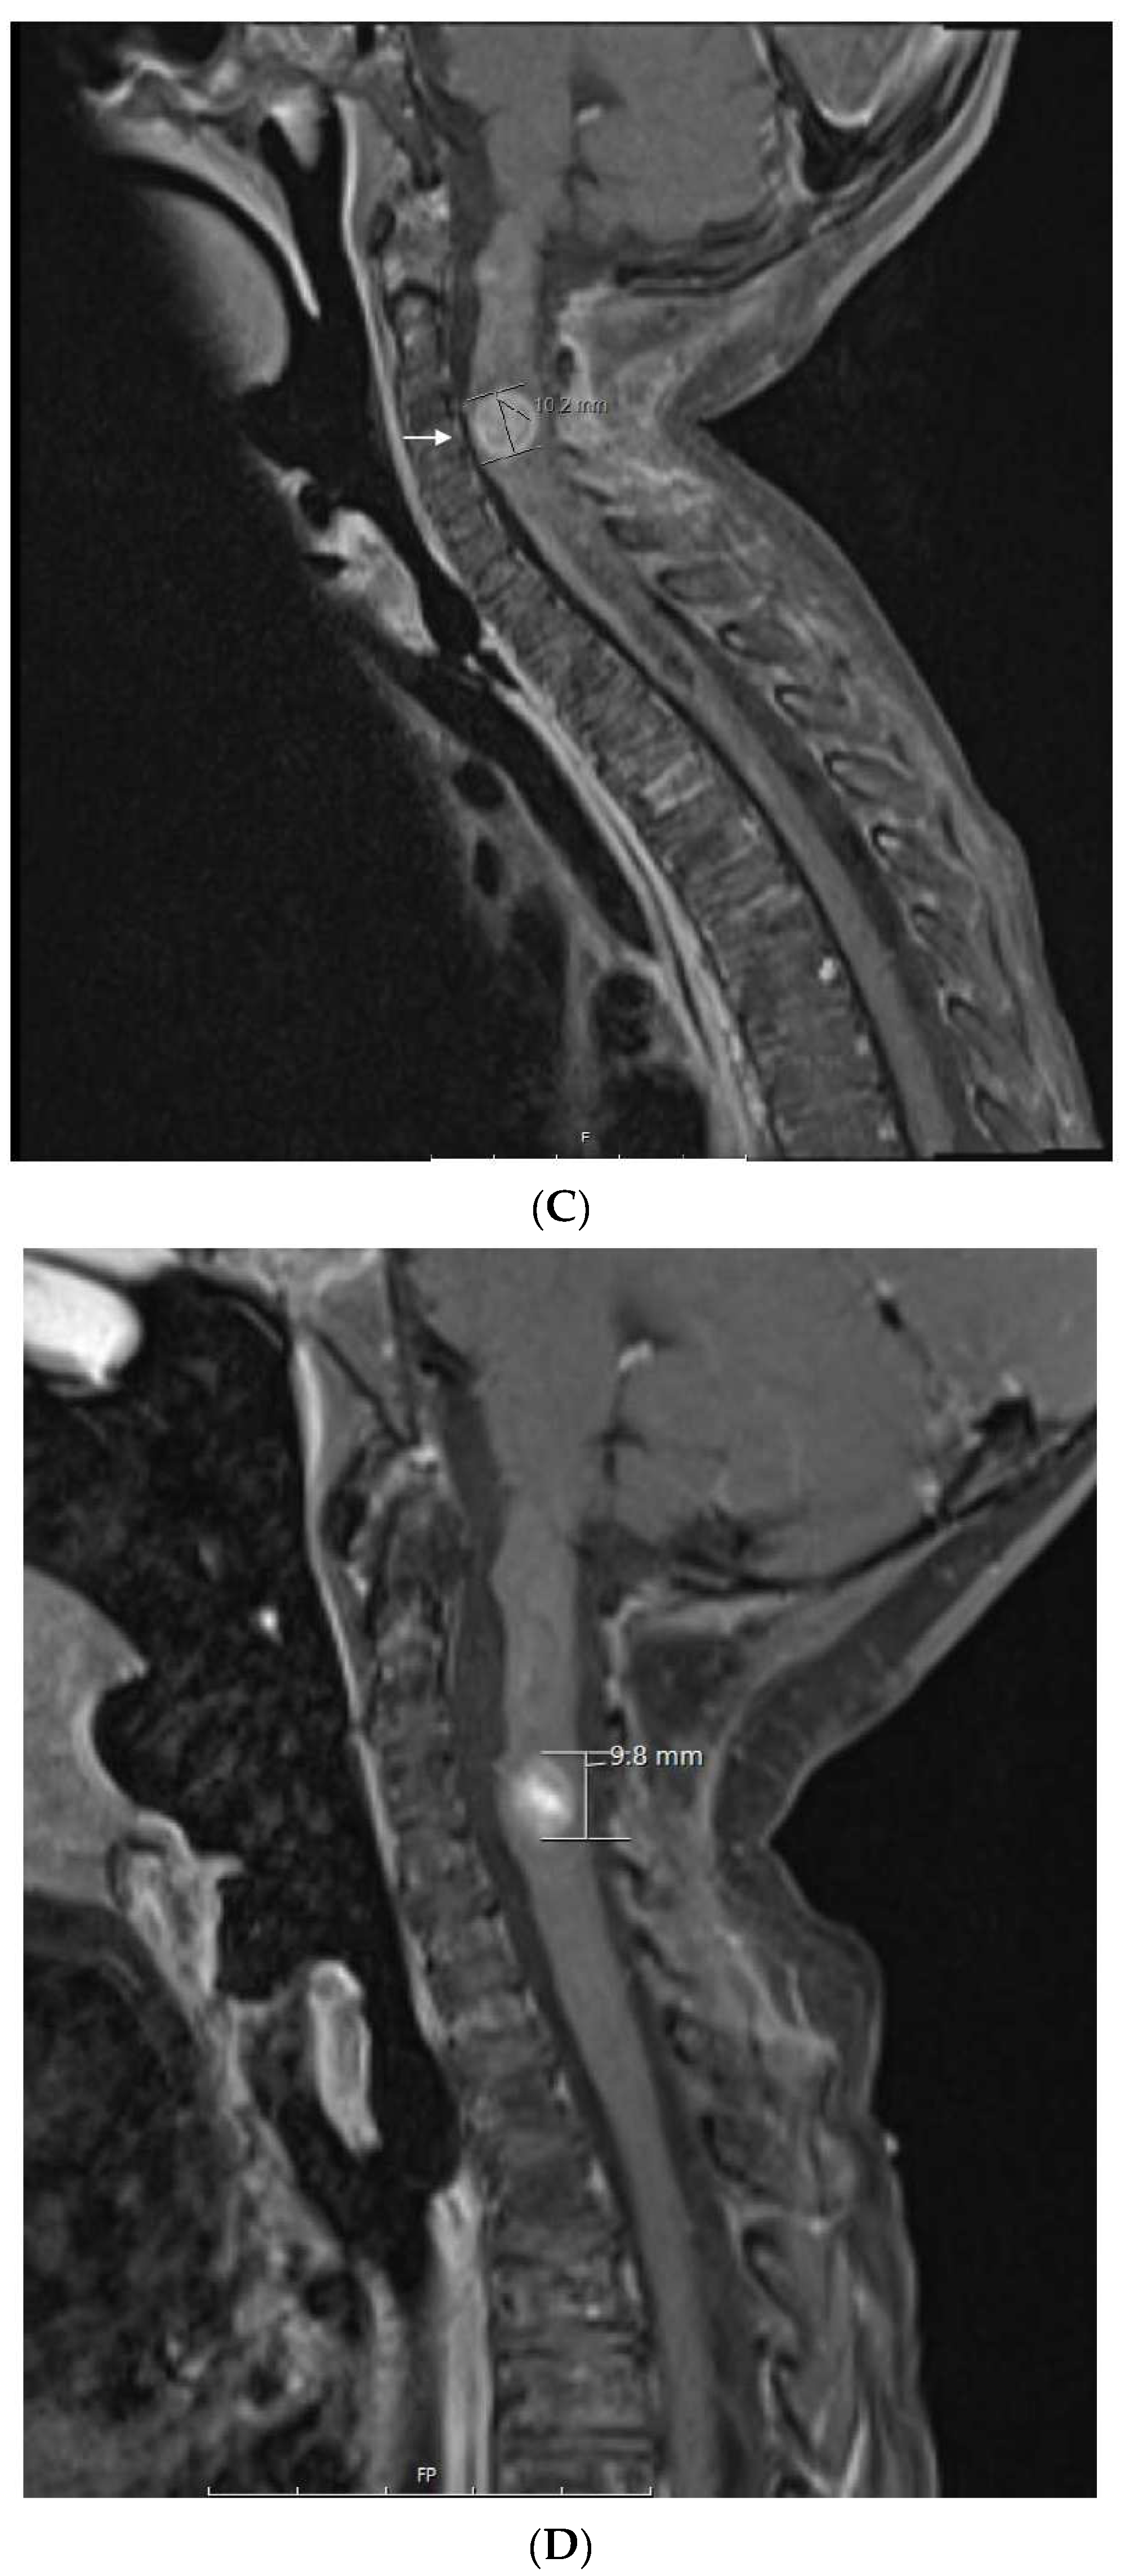

| 2 | Supratentorial Anaplastic Ependymoma. Local and distant relapse to spine. | VP16-CTX, Celecoxib, VA | 6 years | CR | CR 5.5 years at last encounter Alive 8 years at last encounter |

| 3 | Medulloblastoma Infratentorial Microscopic leptomeningeal relapse | VP16 alone (VA added later) | 10 months | CR | CR 5 years at last encounter Alive 7 years at last encounter |

| 6 | Spinal cord neurocytoma Unresectable progressive tumor. | TMZ-CTX, VA, BV, Celecoxib | 3 years | PR | PR at 3 months. Treatment stopped after 4 years of stable disease. PD 10 months later. She remains AWD on treatment |